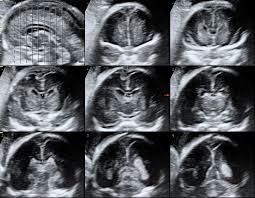

Neurosonography

Neurosonography is a safe, non-invasive, and bedside imaging technique that uses ultrasound to visualize the brain and nervous system, primarily used for diagnosing neonates and infants through the fontanelle.